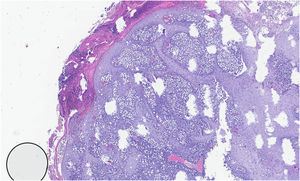

We report the case of a 32-year-old man with an erythematous nodule on the chin, showing central ulceration covered by yellowish exudate and crusts, with a documented progression over three months (Fig. 1). Six months prior, he had travelled to Mexico (Bacalar jungle) and had been previously treated with antibiotics, without improvement. Initial wound cultures isolated Klebsiella aerogenes, prompting treatment with targeted ciprofloxacin for three weeks, with partial improvement. Histopathological examination revealed dermal macrophages containing numerous intracellular Leishmania amastigotes (Figs. 2 and 3), further corroborated by a positive skin culture. L. mexicana was identified by molecular techniques using Internal Transcribed Spacer 1 - Polymerase Chain Reaction - Restriction Fragment Length Polymorphism (ITS1-PCR-RFLP) and Heat Shock Protein 70 (HSP70) sequencing.7 The patient was treated with itraconazole (200 mg every 12 hours) for three months, with complete resolution (Fig. 4). To the best of our knowledge, this is the first identification of CL caused by L. mexicana in Portugal, representing an imported infection. Imported cases of CL caused by L. mexicana complex species have been reported in Europe, though they remain rare.8